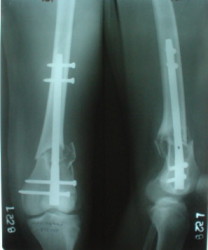

• Re: Перелом "около пластинки"

Отправитель: Alexander Chelnokov 28 Декабрь 2003, 21:01

1

2

de> you think you are using antigrade nails for some very low

de> fractures including some intercondylar fractures.

Exactly. It seems the option looks underestimated.

No, i haven't seen such comparisons. However some advantages of closed antegrade nailing vs conventional plating looks self-evident like no site opeining, no bone skeletization, less blood loss, no need for autografting... If you or other colleagues can help me with the references it would be greatly appreciated. I would be interested also to compare ante- vs retrograde nailing for the localization.

de> And perhaps you could show us also some of your results ,

de> that is (follow up) not immediate postop x rays.

I attached an example of C2 fracture with result of the same technique in 5 months.